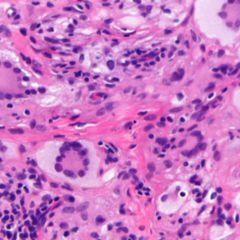

Diagnose

Die Diagnose ergibt sich aus den klinischen Befunden.